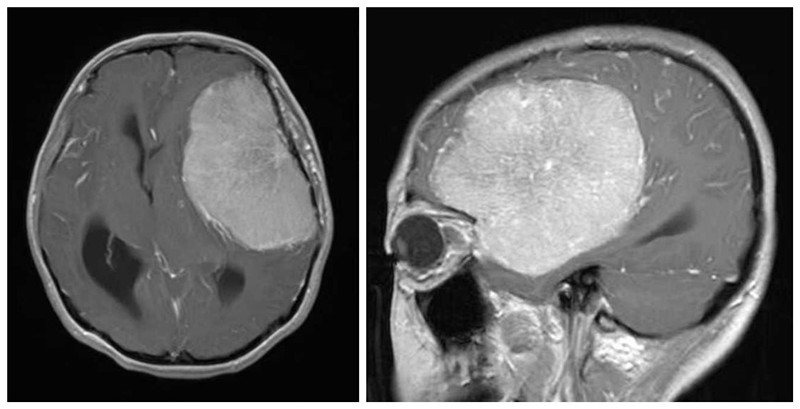

手术当天,时间仿佛变得格外漫长,手术医师聚精会神在显微镜下精细操作,整个手术持续了整整6个小时。每一分钟,都凝聚着医护人员的专注与付出;每一秒钟,都承载着小潘和家人的期待与希望。最终,在神经外科团队与麻醉科手术室团队的共同努力下,手术顺利完成,成功切除了“威胁”小潘生命健康的巨大肿瘤。切除的肿瘤大小达到了94mm×54mm×80mm。

患者术后核磁共振

术后,小潘在医护人员的精心照料下,逐渐恢复。休学1年后,她以顽强的毅力重返校园,继续追逐自己的梦想。如今,距离手术已经过去了2年,小潘回院复查,各项指标恢复良好,复查头颅磁共振脑肿瘤无复发。曾经被疾病困扰的少女,现在已经是一名高三学生,即将踏入大学殿堂,开启人生的新篇章。